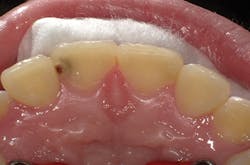

Figure 2

I'll demonstrate this material's versatility with a few cases. First is a large Class III cavity. The patient was extremely apprehensive, so we decided to prepare the cavity using the Lite Touch (AMD Lasers) erbium YAG laser. Very often, as in this case and the next few cases that we will depict, cavity preparation can be performed without anesthetic. In Figure 1, we see the preoperative image of the large Class III cavity on tooth No. 8. Using the Lite Touch laser (figure 2), we were able to excavate the entire cavity in a clean and efficient manner (figure 3). Using a fine diamond, a slight bevel was completed on the enamel at the cavo surface margin. By beveling the enamel, we improve the bond of the adhesive and allow for a seamless blend of the restorative material to the outer tooth structure. In deep restorations such as this, a calcium liner can help minimize sensitivity and act as a buffer between the restoration and pulp. Both Calcimol LC (Voco) and Theracal (Bisco) can be used in this manner. In this case, we decided to use Theracal. Theracal was placed in the deepest area and light-cured for 15 seconds (figure 4). After a 37% phosphoric acid etch of the enamel margin, we applied Futurabond U (Voco) as per the manufacturer's instructions and light-cured for 10 seconds. Admira Fusion shade A2 was placed in three increments and polished. The final restoration exhibits a beautiful luster and a seamless blend from the restoration to the natural tooth (figure 5).